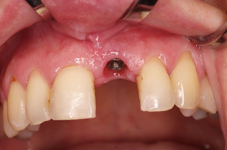

Klasickým příkladem a indikací pro použití implantátu je ztráta jednoho zubu (v tomto případě v předním – frontálním úseku) v jinak zdravém, nepoškozeném chrupu.

Nejčastější příčinou takové ztráty je sportovní nebo dopravní úraz.